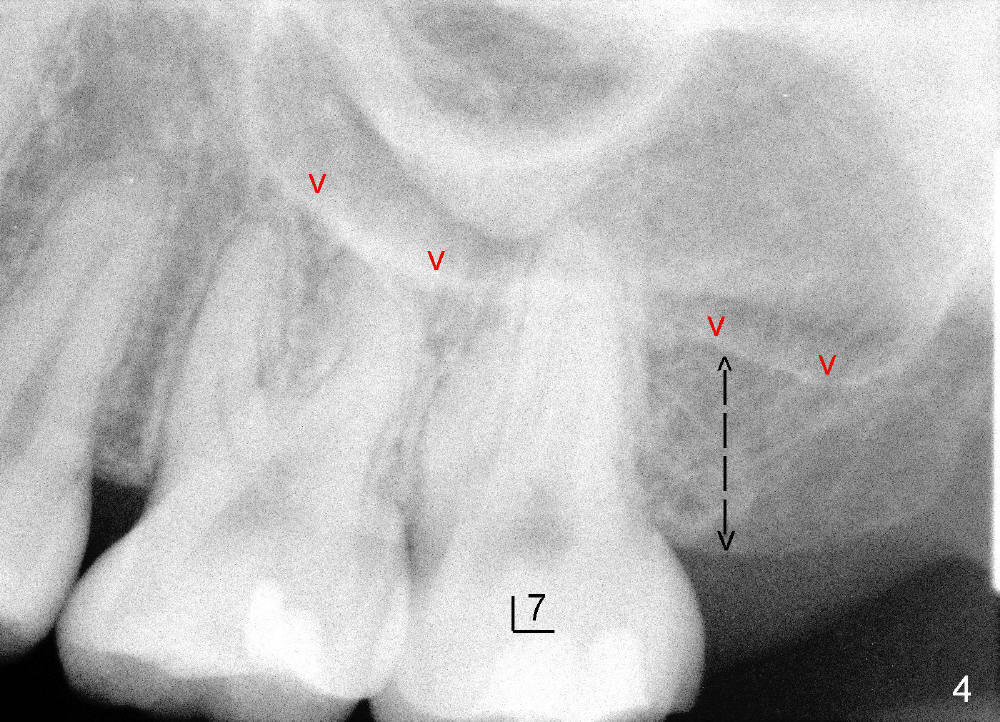

昨天在左上七做根管治疗(图四),二十一岁女孩,嘴巴小,做的很辛苦,术中拍摄根尖片(图五),突然领悟到一个道理。由于上颌窦底板骨皮质明显(图四红箭头),我们认为上颌骨高度仅仅由黑箭头表示。其实一部分根尖深入上颌窦,那里必有骨质,所以上颌骨高度应该由两部分组成(图五:3.46mm

+ 7.54mm),而且最后三个毫米可能对条件不好病例植牙有帮助(例如徐博病例)。